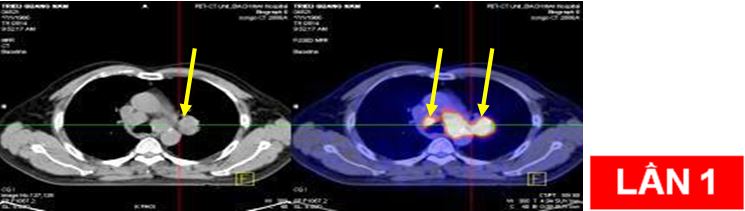

Bệnh nhân:chụp PET/CT lần 2 đánh giá sau 6 chu kỳ hóa chất (có đối chiếu với lần chụp trước khi điều trị).

Sau điều trị: hết u và hạch di căn

Sau điều trị: không thấy nốt mờ và hạch di căn trung thất

Trước và sau điều trị hóa chất 6 chu kỳ